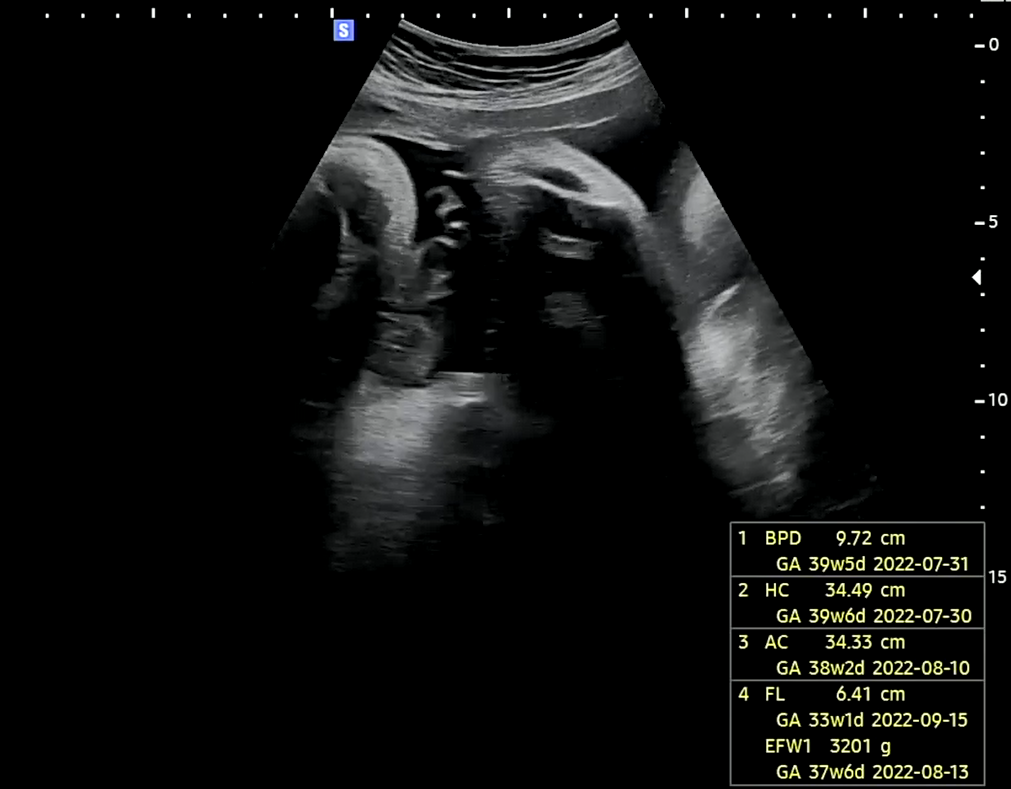

어느덧 36주를 맞이하여 선택제왕날짜를 최종적으로 확정하고 마지막 건강상태를 확인하기 위해 진료를 받으러 병원에 향하였다. 이번에 받은 진료는 태동검사 -> 초음파 진료의 순서였고 태동검사실에 남편은 입장할 수 없었다. 20분가량 진행되는 태동검사를 마치고 바로 초음파 진료를 받으러 갔다.

초음파 진료 후기

1. BPD/HC : 머리 크기 👶 진료 당시 39주 5일차 아기의 크기로 약 3주가량 빠르게 큼

2. AC : 복부둘레 진료 당시 38주 2일차 아기의 크기로 약 2주가량 빠르게 큼

3. FL : 허벅지 길이 진료 당시 약 33주 1일차 크기로 약 3주가량 느리게 큼

4. EFW : 태아 몸무게 진료 당시 37주 6일차 크기로 약 1주가량 빠르게 큼

초음파 진료를 보면서 막달검사 결과를 말씀해 주셨다. 호띵엄마는 문제 없는 상태로 아기를 낳기만 하면 된다고 말씀해주셔서 내심 안심이 되었다. 또한 마지막 진료이기에 아기를 낳기전에 손목 보호대를 병원에서 구입하고자 의사선생님께 처방을 요청하였더니 흔쾌히 손목보호대 1개를 처방해주셨다. 제왕 절개후 산모가 문제될 수 있을 것들을 설명해주신 후 수술동의서를 작성하는 중에 살짝 걱정이 되어 눈가에 눈물이 맺혔다. 그렇지만 그런 안좋은 일은 없을 것이라 당연스럽게 생각하고 있다. 호띵이 태동을 보면 가끔 심하고 대체적으로 조용한 것을 미루어보아 순딩이일 것으로 예측된다. 이 날 최종 검진비용은 손목보호대 포함 46,500원이었다.